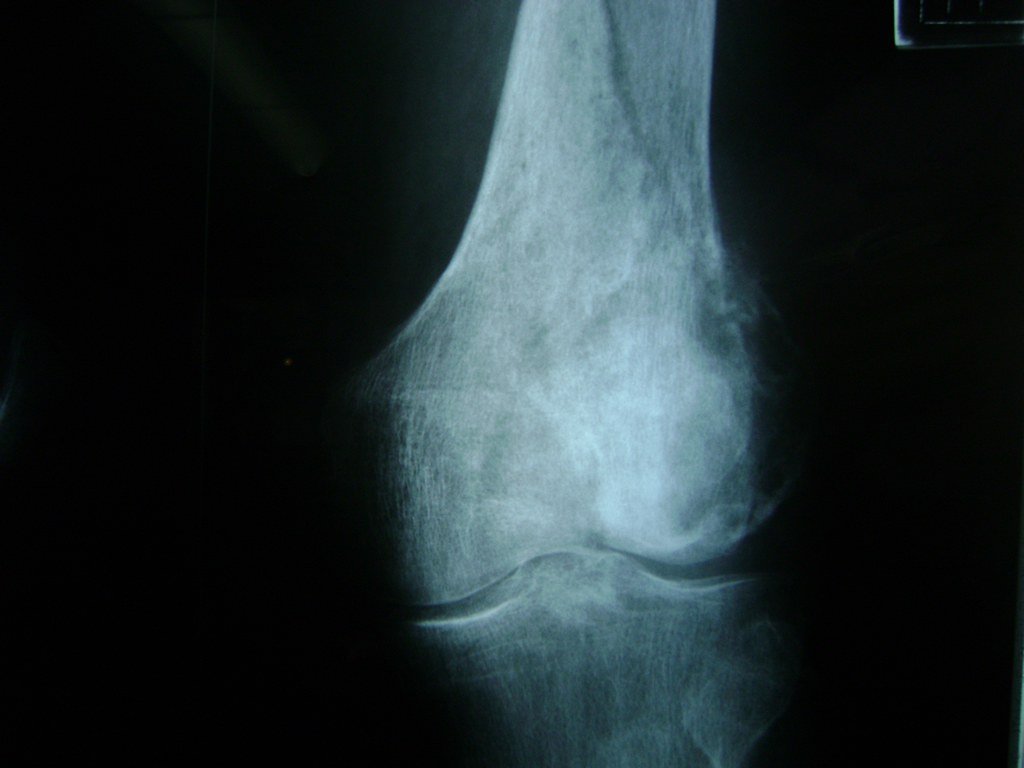

Cirugía de Tibia y Peroné

La artroscopia de rodilla es un cirugía en el cual la estructura interna de la articulación es examinada ya sea para realizar un diagnostico o para realizar un tratamiento, este procedimiento se realiza utilizando un instrumento parecido a un pequeño tubo llamado artroscopio.